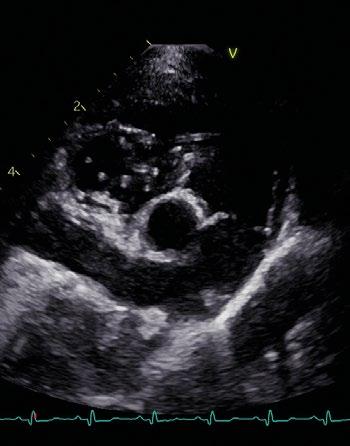

Utilidad clínica de la ecografía pulmonar y cardiaca en urgencias